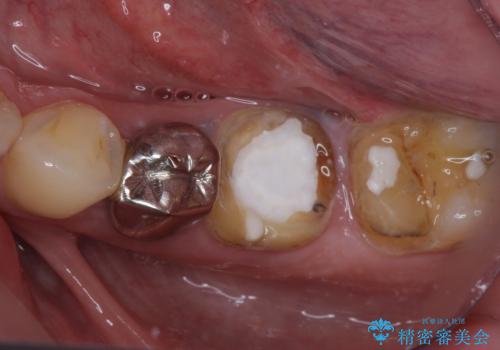

欠損と治療途中の奥歯 インプラント治療と補綴治療

- 下顎左右の奥歯を治療途中で放置してしまっているとのことで来院された患者様です。

欠損部はインプラントによる補綴治療を、土台の外れてしまった歯は、根管治療を行った上で、補綴治療を行うこととしました。